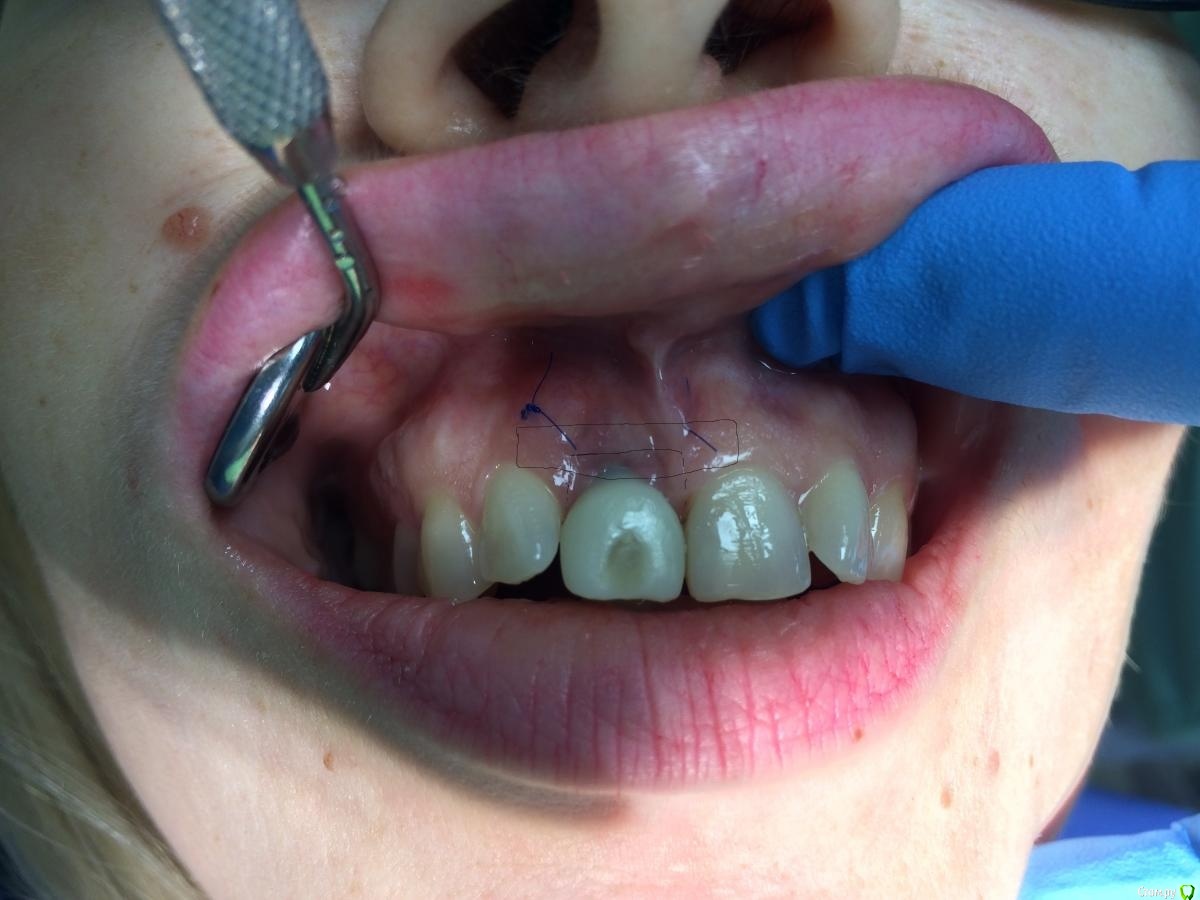

Doctor Vlad Опубликовано 2 февраля, 2021 Автор Поделиться Опубликовано 2 февраля, 2021 Ну как там дела? Я сегодня вспомнил Ваш случайОго,а я думал че икал вчера)) Она была на осмотре до нового года. В корональной части там где был пергамент по толщине я потерял. Но это и без операции ушло бы. Возможно это как-то связано с толщиной временной коронки. Я ее истончил, но не достаточно, на мой взгляд. Это к теме о поддержать протетикой. Отправил ее гулять на 2 месяца. потом думаю коронально смещать и еще добавлять. Чтобы высоту исправить. Ссылка на комментарий

Doctor Vlad Опубликовано 2 февраля, 2021 Автор Поделиться Опубликовано 2 февраля, 2021 здесь в корональной части получше, опять все гладилкой отслоили)? Ссылка на комментарий

колесников Опубликовано 2 февраля, 2021 Поделиться Опубликовано 2 февраля, 2021 Я же писал,гладилка,скальпель15С,пинцет-вот все что нужно для работы. Правда тут был перионож,под углом в шахту не удавалось войти.Все хорошо у Вас. Надо подождать. Я думаю подрастёт. И ещё добавить . Расщеплять будет уже веселее. Красивый профиль сделали на реставрации. Но! Этот уступ 1мм! Он все портит. Или пилить юбку или брать высотой 3мм Ссылка на комментарий

Doctor Vlad Опубликовано 3 февраля, 2021 Автор Поделиться Опубликовано 3 февраля, 2021 Я же писал,гладилка,скальпель15С,пинцет-вот все что нужно для работы. Правда тут был перионож,под углом в шахту не удавалось войти.Все хорошо у Вас. Надо подождать. Я думаю подрастёт. И ещё добавить . Расщеплять будет уже веселее.Красивый профиль сделали на реставрации. Но! Этот уступ 1мм! Он все портит. Или пилить юбку или брать высотой 3ммНа рисунке отразил, если правильно понял? два варианта как убрать уступ. 1 и 2. Но это лучше делать на следующем этапе, теперь.Коронально смещенный с расщеплением и сст и с композитными каплями на контакт коронки Ссылка на комментарий